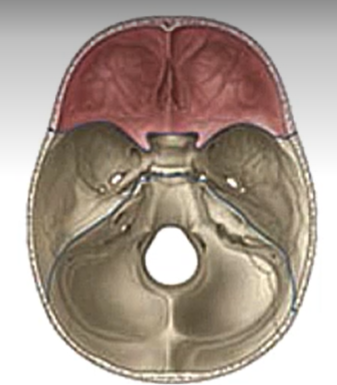

What is this?

Anterior cranial fossa

What is being drawn over in red?

Dural folds